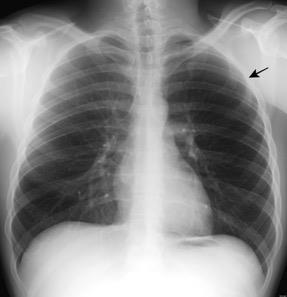

Tumor desmoide (“Fibromatosis agresiva”)

T1: Isointensos con músculos.

T2: Señal intermedia y de alta intensidad.

Presencia frecuente de áreas curvilíneas y lineales dentro de la lesión

Mansour J et al. Diagnostic and Imaging Approaches to Chest Wall Lesions. Radiographics 2022